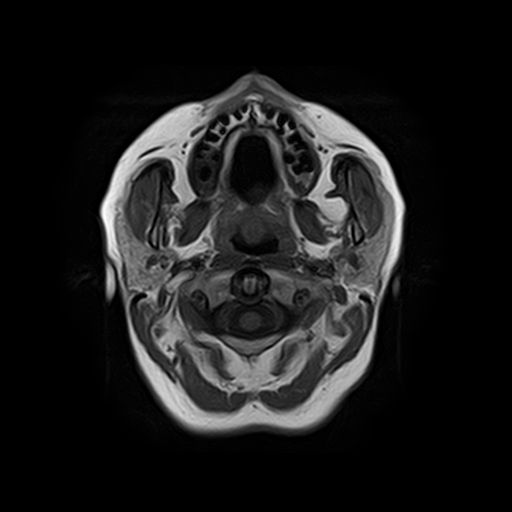

Височно-нижнечелюстной сустав является парным комбинированным суставом и имеет сложное строение. В него входят суставные ямки височной кости, суставные головки нижней челюсти и расположенные между ними хрящевые пластинки – мениски, выполняющие роль амортизаторов.

Чаще всего дисфункция височно-нижнечелюстного сустава обусловлена внутренним повреждением, смещением мениска и суставной головки нижней челюсти. Для определения степени смещения внутрисуставных структур выполняется функциональная проба с проведением МРТ в двух положениях:

Магнитно-резонансная томография является наиболее точным и эффективным методом диагностики поражения височно-нижнечелюстных суставов, так как позволяет получить детальную информацию о состоянии не только костей, но и связочного аппарата, хрящей, менисков, жевательных мышц, окружающих мягких тканей.

При проведении магнитно-резонансной томографии на изображениях визуализируются: височная кость, головка мыщелкового отростка нижней челюсти, суставная щель. Помимо костных структур МРТ позволяет оценить состояние мягких тканей – внутрисуставного диска и связочного аппарата височно-нижнечелюстного сустава, жевательных мышц.